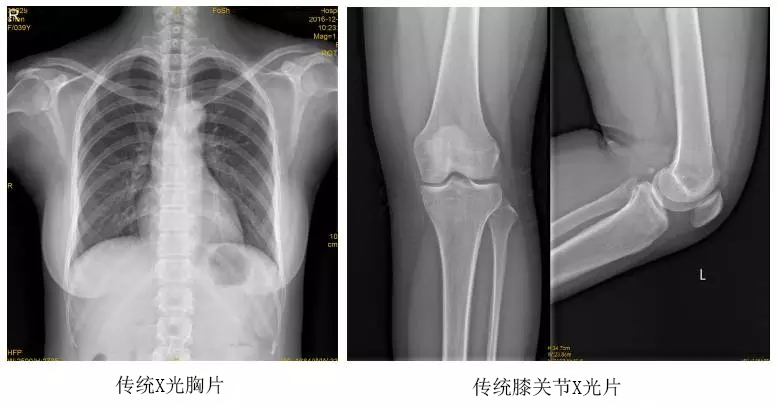

臨床在診治脊柱及下肢畸形時(shí),往往采取矯正手術(shù)治療。這就需要在對(duì)其進(jìn)行手術(shù)前后,拍攝全脊柱或全下肢的X光片作為診治依據(jù),以便分析病情、制定手術(shù)方案和評(píng)估術(shù)后療效。目前大部分醫(yī)院使用的DR攝片機(jī),因拍攝幅面受限,最大規(guī)格43cm,但成人的全脊柱長度一般約60cm,而全下肢更長,不能一次性拍攝出完整的全脊柱或全下肢的X光影像。以全脊柱攝片為例,各拍攝一張傳統(tǒng)的頸椎、胸椎、腰椎的X片雖然就能觀察到每個(gè)部位局部的側(cè)彎情況,但不能觀察到三者之間的連續(xù)性。因此傳統(tǒng)X光片在這類疾病診斷上存在著一定的缺陷,無法更精準(zhǔn)有效地進(jìn)行臨床診斷和治療。

以某院所攝X光片為例,對(duì)比傳統(tǒng)攝片與全身拼接功能的區(qū)別:

傳統(tǒng)X光片只能觀察每個(gè)部位的局部情況,無法在統(tǒng)一體上進(jìn)行連續(xù)、全面的觀察,全脊柱及下肢全長片則能直觀的看到整體形變。通過DR全身拼接功能實(shí)現(xiàn)的完整成像,為診治脊柱及下肢畸形提供了完美的臨床影像依據(jù),對(duì)臨床診斷、術(shù)前手術(shù)方案的制定和術(shù)后療效的評(píng)估等臨床應(yīng)用具有十分重要的意義,有效滿足了此類疾病臨床診斷和治療的要求。